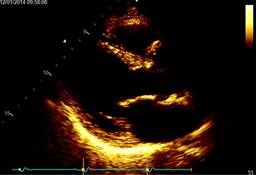

After measuring the aortic sinus defect, a piece of autologous pericardium was meticulously prepared and tailored according to the measurements and shape of the defect, carefully suturing the pericardial patch continuously to the aortic defect with Prolene 5-0, confirming no-insufficiency of the valve finally weaning the patient from cardiopulmonary bypass as usual. After surgery, the patient recovered with minimal analgesic drugs requirement, removing the chest tube and the pacing wires on the second postoperative day and discharged to home on the fourth postoperative day, without complications at follow up, when he had a significantly modified sinus of Valsalva aspect (Figure 5).

Figure 5: Postoperative transthoracic echocardiogram in parasternal view with a mild aortic insufficiency, as before surgery.